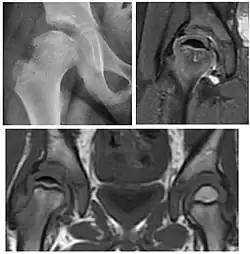

Most of the angles and measurements described in the plain radiograph section can be accurately reproduced on MRI. In addition, the superiority of MRI resolution with intra-articular contrast allows detection of labral and chondral abnormalities that may influence the choice of medical, percutaneous, or surgical management (Figure 9).[1]

Figure 9:

Sagittal T1 weighted image showing anterosuperior labral tear.[1] -

Sagittal T1 weighted image showing chondral lesion.[1] -

Sagittal CT-arthrography showing posteroinferior chondral injury.[1] -

Coronal CT-arthrography (d) showing ligamentum teres tear.[1]

MR arthrography has proven superior in accuracy when compared to native MR imaging. It is considered the best technique to assess the labrum. Knowledge of the normal variable morphology of the labrum helps to differentiate tears from normal variants. A triangular shape is most commonly seen in 66% of asymptomatic volunteers, but round, flattened, and absent labra can also be found in asymptomatic populations. MR arthrography has demonstrated sensitivity over 90% and specificity close to 100% in detecting labral tears. Loose bodies are demonstrated as filling defects surrounded by the hyperintense gadolinium.[1]

Association between labral tears and chondral damage has been demonstrated. This underscores the interaction between cartilage and labrum damage in the progression of osteoarthritis. Chondral damage to the posteroinferior part of the acetabulum as a contrecoup lesion occurs in approximately one-third of pincer cases secondary to persistent abutment on the anterior part of the joint leading to a slight posteroinferior subluxation. This is considered a bad prognosis sign.[1]

MR arthrography can also demonstrate ligamentum teres rupture or capsular laxity, which are debated causes of microinstability of the hip. Elongation of the capsule or injury to the iliofemoral ligament or labrum may be secondary to microtrauma in athletes. MR can demonstrate abnormalities in these cases, such as increased joint volume or a ligamentum teres tear (Figure 9).[1]